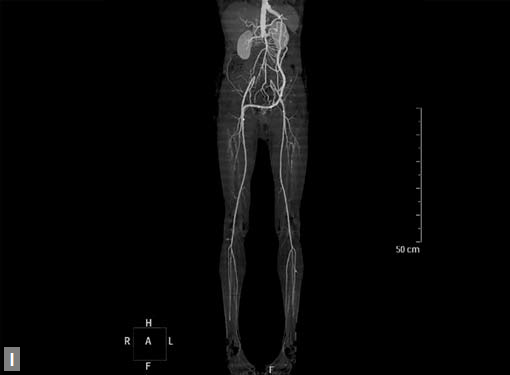

Figs 19A to Y (A to C) Scannogram (A), plain (B) and contrast study (C) show partial anomalous pulmonary venous connection; (D to F) Heterotaxy; (G) Aortic occlusion; (H and I) Aortic stents; (J) Aortic dissection with ‘Benz’ sign due to second dissection within the true lumen; (K, L and M) Aortic dissection with thrombus in pseudolumen following catheter angiogram; (N) Aortic dissection involving common carotid arteries and subclavian artery; (O, P, Q and R) Aortic dissection with right renal artery arising from true lumen and left renal artery from false lumen; (S, T, U and V) Stanford B dissection with extension Y to iliac vessels; (W to Y) Aneurysmal dilation of ascending aorta